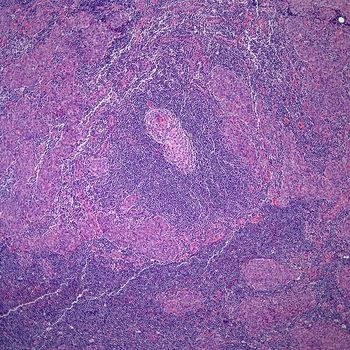

A 56-year-old man presents with an intranasal mass. What is your diagnosis?